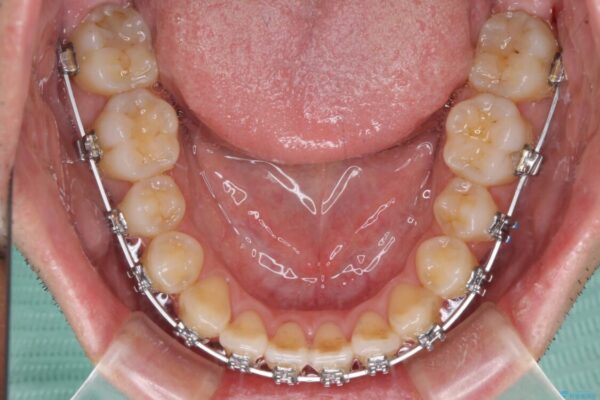

治療途中

• 左右の八重歯が気になる ワイヤー装置での咬み合わせ改善 治療途中画像